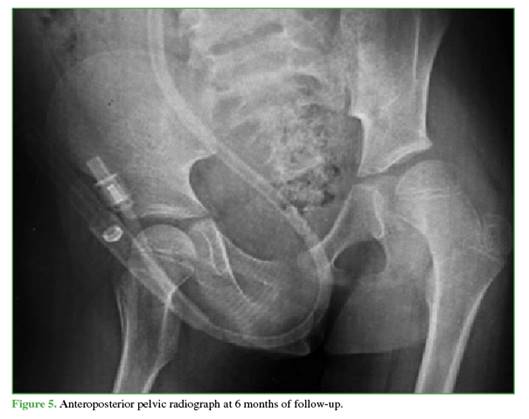

Follow-up radiographs at 3 (Figure 4) and 6 months (Figure 5) showed no evidence of AVN, and other musculo-skeletal complications associated with traumatic dislocation were also ruled out.

Follow-up radiographs showed no signs suggestive of AVN (sclerosis, collapse, cysts, joint-space narrowing, etc.).22 These findings may take 2 to 6 months to become visible on radiographs,20 so the follow-up schedule was appropriate.

Despite the absence of radiological signs of AVN up to 6 months, continued imaging follow-up is necessary to detect potential development of AVN, which may take up to 2 years to manifest.25